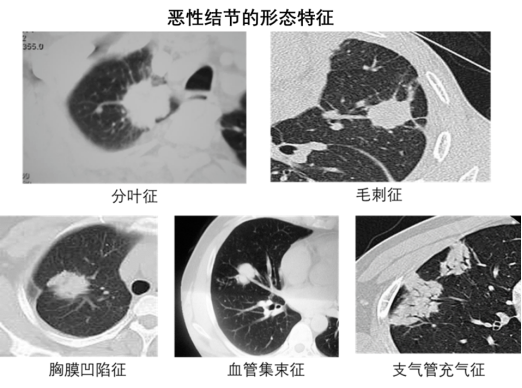

● 惡性征象:磨玻璃結(jié)節(jié)(尤其是混合磨玻璃結(jié)節(jié))、邊緣分葉狀、有毛刺、胸膜牽拉、內(nèi)部密度不均勻;

● 良性征象:邊緣光滑、內(nèi)部鈣化(如 “爆米花狀” 鈣化多為錯構(gòu)瘤)、密度均勻的實性結(jié)節(jié)。